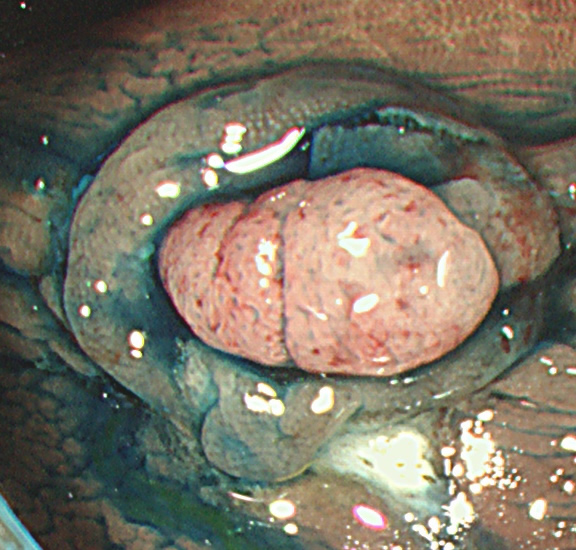

コールド法で切除された検体は「目玉焼き」のようになります。「黄身」が病変で、「白み」が周囲の正常組織(余白、マージン)です。

腫瘍の取り残しを防ぐために「白み(余白)の大きな目玉焼き」にすることが、コールド法の最大のポイントであり、技術的に最も難しい部分です。